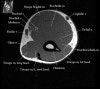

2. Axial section

1) The tendons of the Biceps Brachii and Brachiallis muscles transversely as they insert onto the Radius and Ulna respectively. 2) The distal Triceps tendon is also well evlauated in this plane.